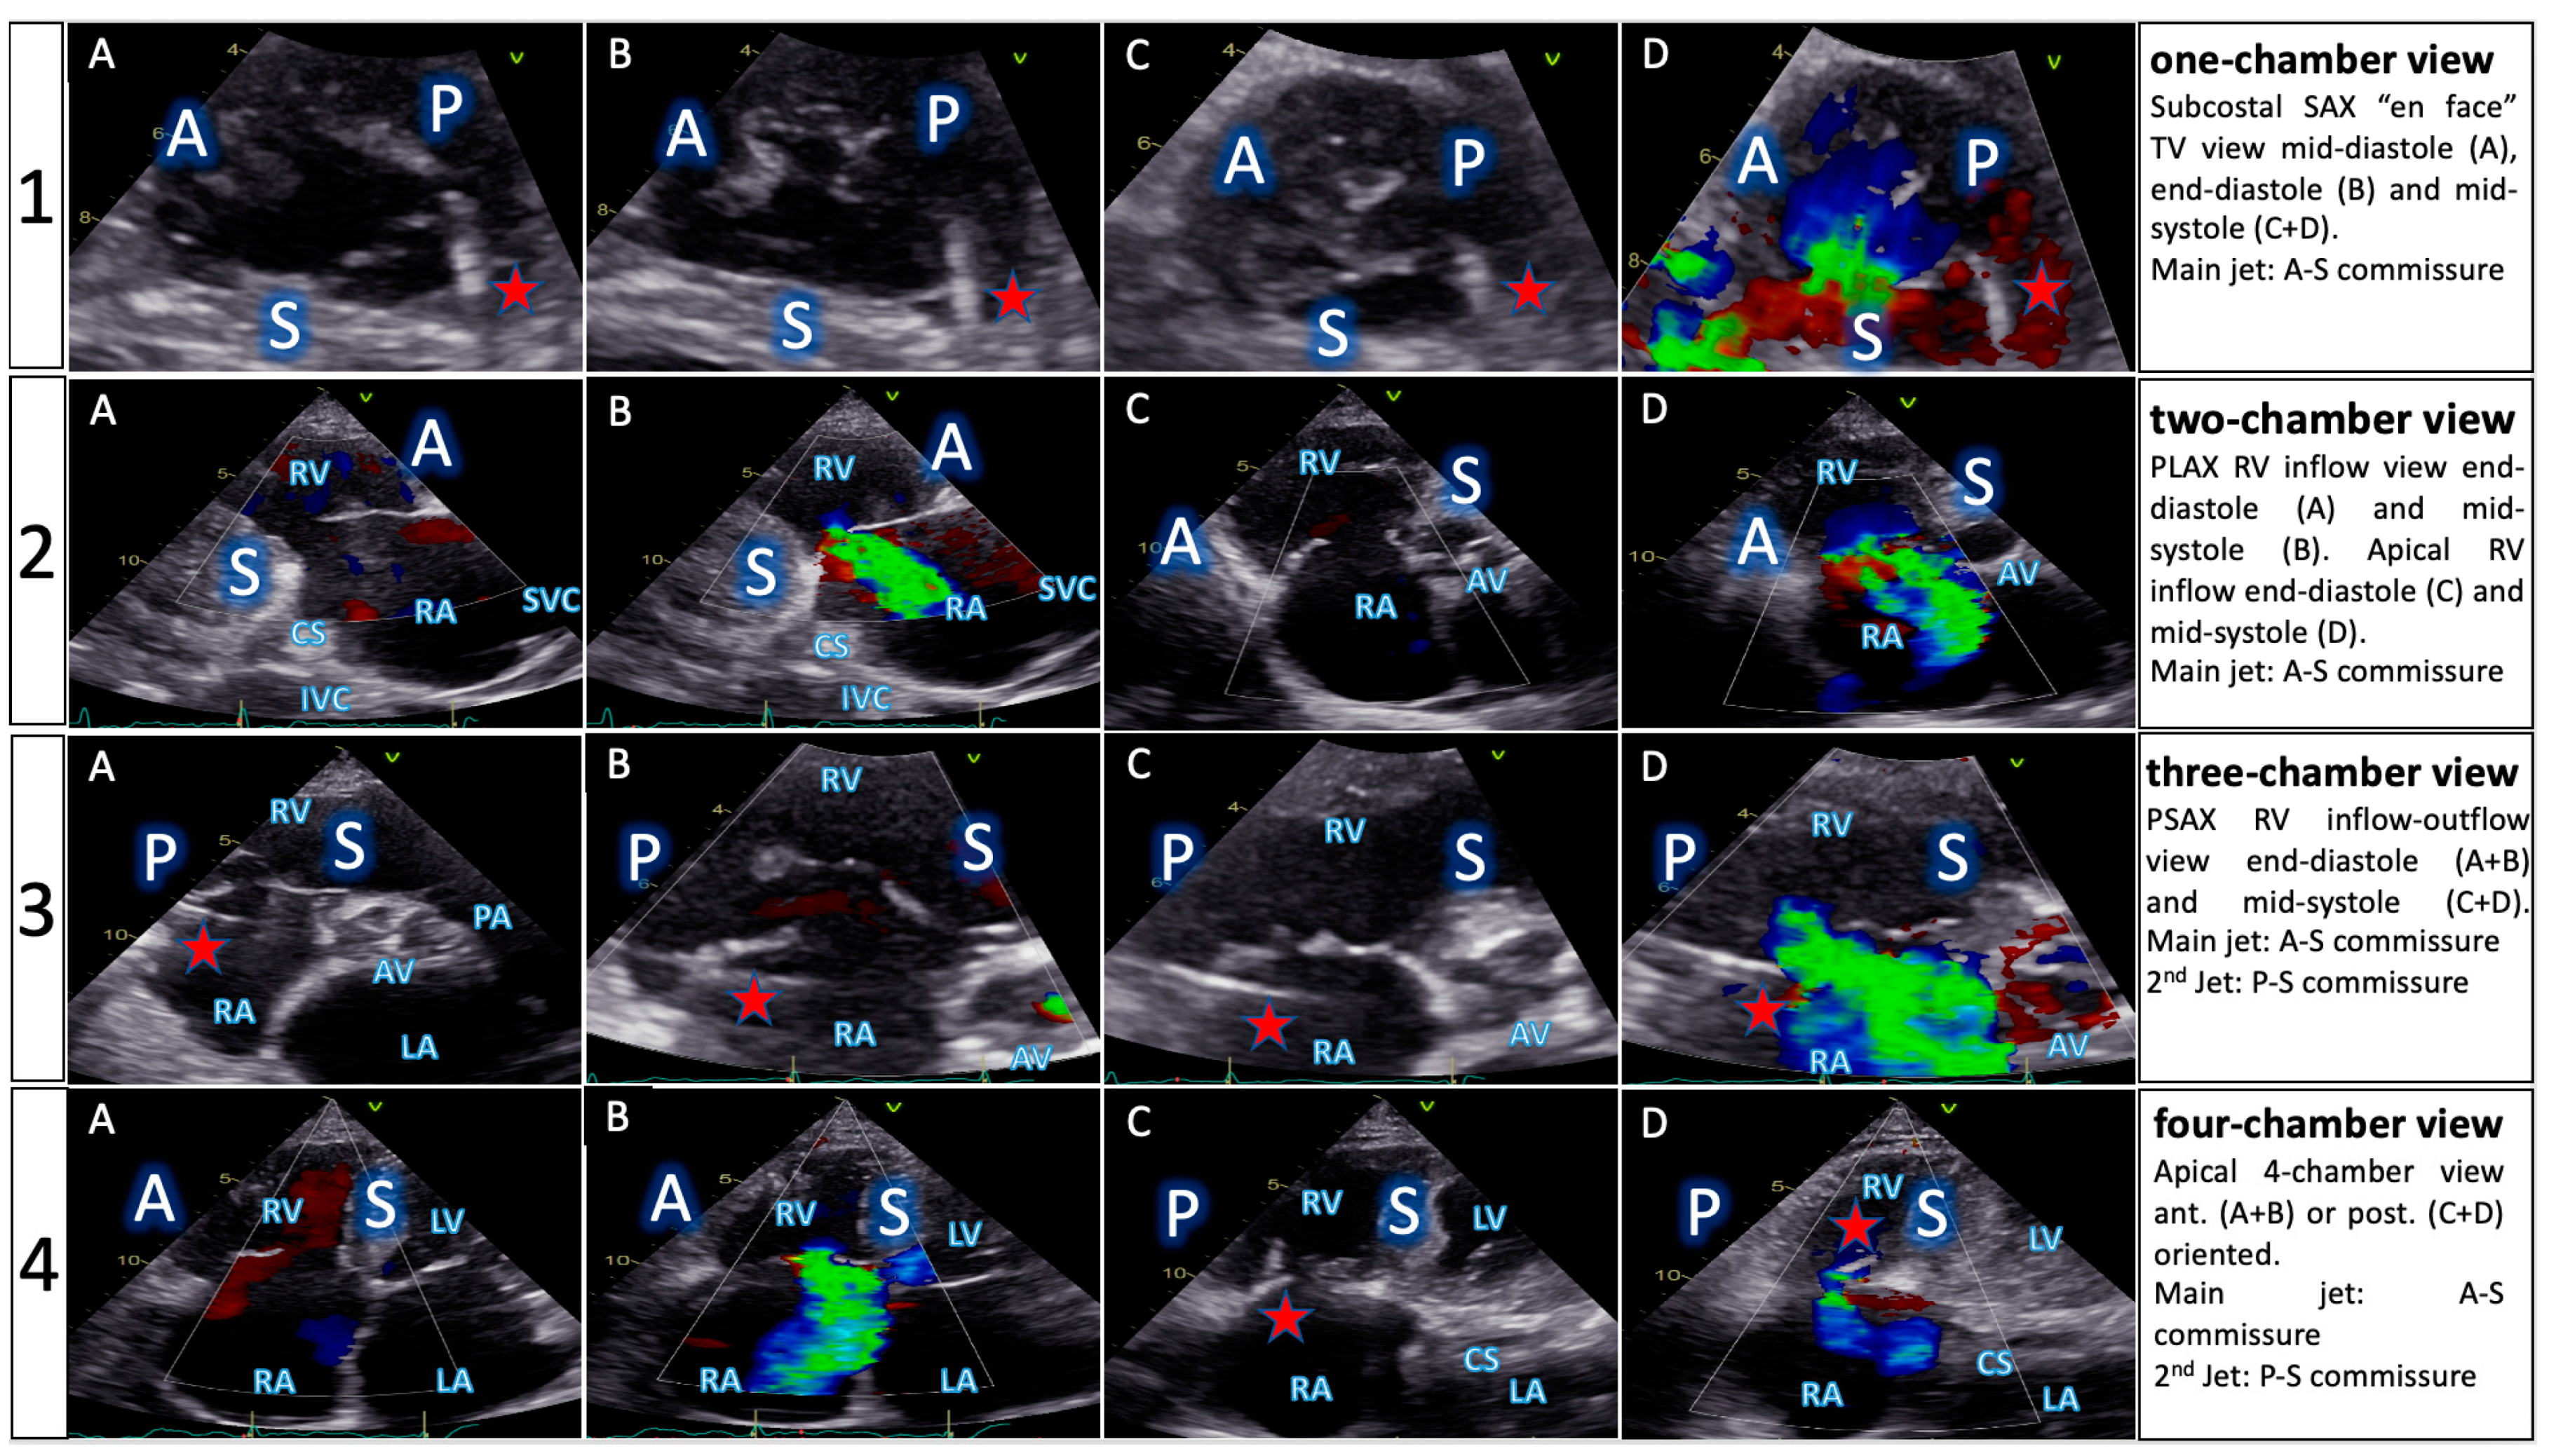

- The implementation of the concept of the four right-sided chamber views builds a bridge between imaging methods involved in procedural planning and interventional guidance. Furthermore, it allows cardiac imaging specialists and interventionalists to speak a common language.

| TTE View | Focus | ||

|---|---|---|---|

| Functional Parameters | Right Heart Morphology | TV Anatomy | |

| PLA standard | LVOT diameter (Qs/CO calculation) | RV function and size (eyeballing) | -- |

| PLA RV inflow RH two-chamber view | TR severity (eyeballing) TR Jet VC and PISA (optional) | RV function and size (eyeballing) | AL visualization SL vs. PL distinction |

| PSA standard RH three-chamber view | TR severity (eyeballing) RVOT VTI RVOT diameter | RV size PA size | Leaflet distinction, if possible |

| PSA-modified alternative RH one-chamber view | TR severity (eyeballing) | TV annulus size Coaptation gap | Simultaneous visualization of all leaflets |

| A4C RH four-chamber view | TR Jet area, VC and PISA TR VTI, RVSP TAPSE RV free wall TDI RV FAC RA volume RV diameters LVOT VTI (A5C/A3C) | RV function and size RA size TV annulus size Tenting height | SL visualization AL vs. PL distinction |

| A2C right alternative RH two-chamber view | TR Jet area, VC and PISA | RA size TV annulus size | AL visualization |

| Subcostal long axis | Hepatic systolic vein flow reversal Inferior vena cava size | RV function and size (eyeballing) | PL visualization AL vs. SL distinction |

| Subcostal short axis RH one-chamber view | TR severity (eyeballing) | Coaptation gap | Simultaneous visualization of all leaflets |